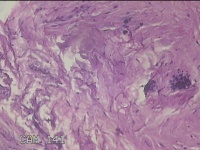

右颈部皮肤肿物

性别

女

年龄

29岁

临床诊断

纤维瘤

一般病史

右颈部皮肤起肿物10年左右。

标本名称

大体所见

灰白暗红色肿物0.3x0.2x0.1cm一个,表面光滑。

图2